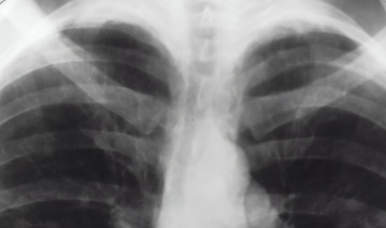

LungDetect AI: Detection of Infectious Lung Diseases from X-Rays

Improving medical diagnosis by using computer vision systems to detect

pneumonia from chest X-rays.